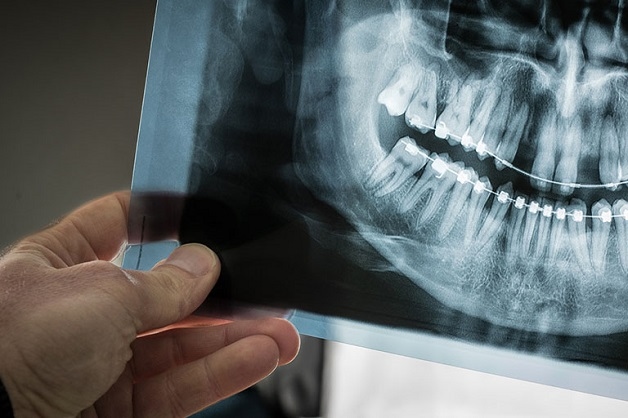

Hình ảnh chụp X quang sẽ giúp cho bác sĩ có hình ảnh trực quan, chính xác về tình trạng bệnh

Khi răng khôn mọc sẽ gây nên nhiều vấn đề về sức khỏe, tâm lý hoặc thẩm mỹ, vì vậy người bệnh nên tới gặp bác sĩ để được chẩn đoán. Khi đó, chụp X quang cho răng khôn là rất cần thiết. Bởi thông qua hình ảnh chụp này, kết hợp với thăm khám tổng quát bên ngoài, bác sĩ sẽ xác định được hướng mọc, vị trí mọc hoặc những tổn thương ở bên trong – ngoài của răng. Việc thăm khám bằng mắt thường sẽ không thể nhìn thấy được điều này.

Chụp X quang răng cũng tương tự chụp X-quang ở các bộ phận khác. Hình ảnh chụp sẽ giúp cho bác sĩ có hình ảnh trực quan, chính xác về tình trạng bệnh cũng như đưa ra được chẩn đoán, cách điều trị phù hợp.